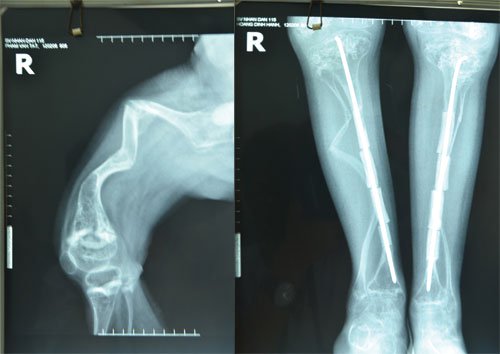

Thực hiện chụp X-quang, xét nghiệm về collagen (lấy mẫu bệnh phẩm từ da) hoặc Xét nghiệm gen (lấy mẫu máu).

Cho đến nay vẫn chưa có phương pháp điều trị đặc hiệu cho căn bệnh này. Phẫu thuật (xuyên đinh), vật lý trị liệu, chăm sóc đúng cách và lối sống lành mạnh sẽ góp phần giúp đỡ những người bị bệnh xương thủy tinh.

Click vào ảnh để xem 4 hình ảnh minh họa